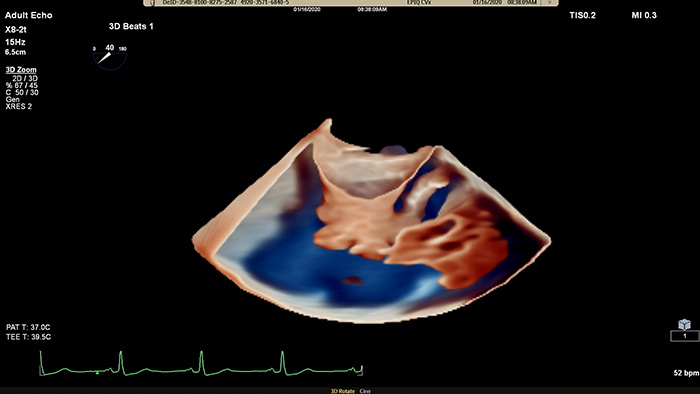

Philips Cardiac TrueVue on EPIQ CVx.

Visualize cardiac morphology using ultrasound with TrueVue Glass